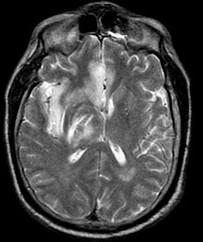

问题 26岁女性,既往体健,突发精神恍惚,癫痫发作。血压100/60mmHg,体温37.3℃,腰穿压力常,脑脊液无色透明,白细胞20个/mm,均为淋巴细胞,糖及蛋白正常。头MRI显示如图。病原体可能是 ( )

选项 A、柯萨奇病毒 B、脊髓灰质炎病毒 C、流感病毒 D、埃可病毒 E、HSV 一、单项选择题

答案 E